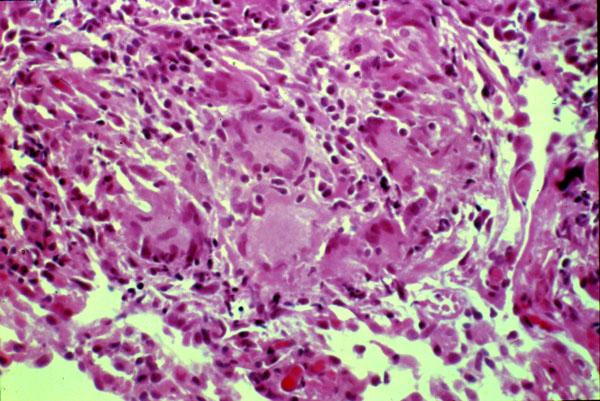

This high power shows an interstitial non-caseating

granuloma

. When granulomas are prominant, it may be difficult to distinguish this from sarcoid.